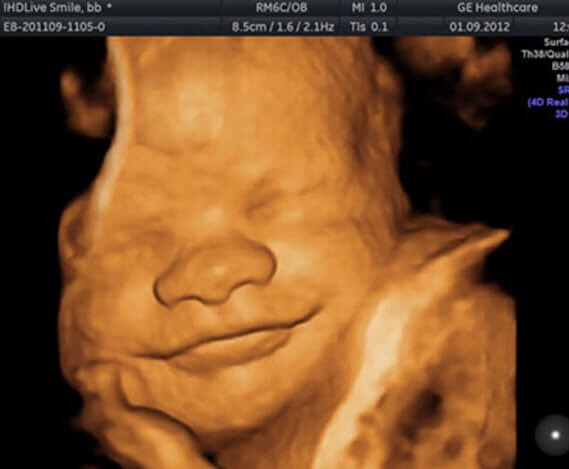

Взято на просторах интернета. Прикрепила для мимо проходящих глаз постов))

Что за улыбашка!)))) Ягодка прям)))